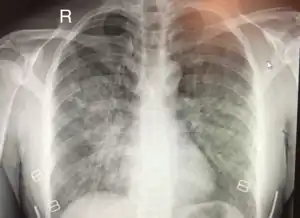

| Chest x-ray of HAPE showing characteristic patchy alveolar infiltrates with right middle lobe predominance. | |

Hypoxic pulmonary vasoconstriction (HPV) occurs diffusely, leading to arterial vasoconstriction in all areas of the lung. This is evidenced by the appearance of "diffuse," "fluffy," and "patchy" infiltrates described on imaging studies of climbers with known HAPE.[9]

On physical exam, increased breathing rates, increased heart rates, and a low-grade fever 38.5o (101.3o F) are common.[9][10] Listening to the lungs may reveal crackles in one or both lungs, often starting in the right middle lobe.[9][10] This can be seen on X-ray and CT imaging of the chest.[9][10] One distinct feature of HAPE is that pulse oximetry saturation levels (SpO2) are often decreased from what would be expected for the altitude. People typically do not appear as ill as SpO2 and chest X-ray films would suggest.[9][10] Giving extra oxygen rapidly improves symptoms and SpO2 values; in the setting of infiltrative changes on chest X-ray, this is nearly pathognomonic for HAPE.[10]